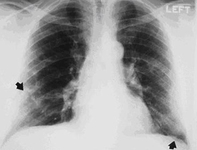

Asbestosis

Posterior-anterior view of the chest with 'mesa'-like pleural thickening of the left diaphragm and 'in-profile' pleural thickening of the mid zones of both the left and right lungs

From the personal collection of Kenneth D. Rosenman MD